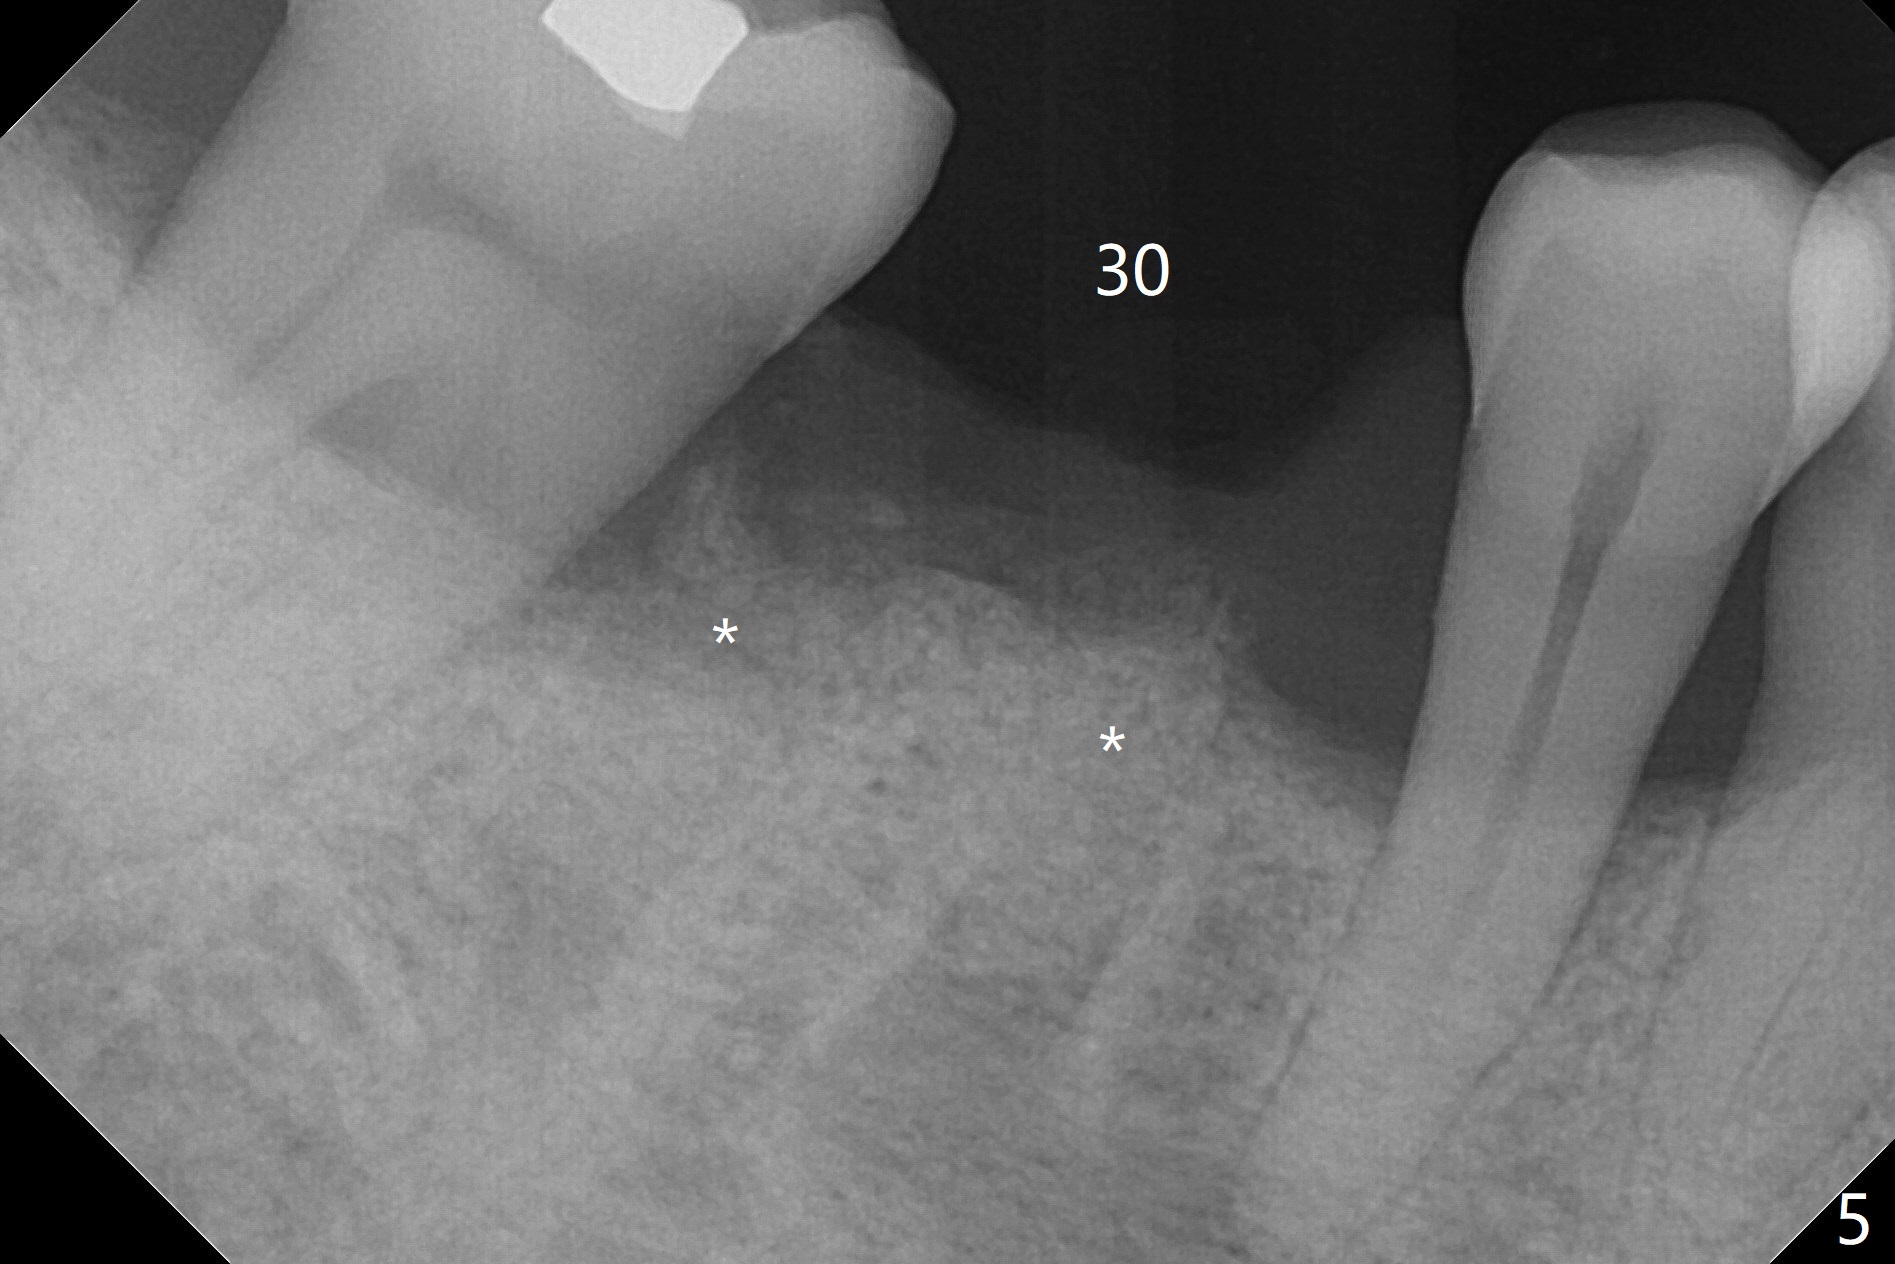

A 60-year-old man (smoker, 1/3 to 1/2 ppd) with large DO amalgam at #30 develops pain and mild swelling apparently apical to #29 (Fig.1-3). Both teeth (having fused PARL (periapical radiolucency) *) have mild percussion with the tooth #29 having higher mobility. CBCT shows apical defect (Fig.3 >). Three weeks earlier, the tooth #19 had much more severe infection with a similar apical defect (Fig.4 >). Combined with history of repeated infection associated with #30, the tooth is extracted with difficulty in obtain sound anesthesia. Socket preservation is performed instead of immediate implant (Fig.5 (*: Vanilla Graft)). CBCT makes it easy to diagnose 2 canals at #28 (Fig.6 as compared to Fig.2). Pain gradually decreases 3 days postop. In fact he has hypertension and smokes.

The bone seems to be wide to hold a 5x11.5 mm implant if it is placed early post extraction (Fig.7). Probably due to smoking, the socket appears to heal slow (Fig.8,9). There is mild palpation pain in the buccal vestibule. The tooth #29 remains mobile. The patient is scheduled to return for follow up in 2 months. A 5x5 cm scan is taken for the lower right posterior area for guided surgery.